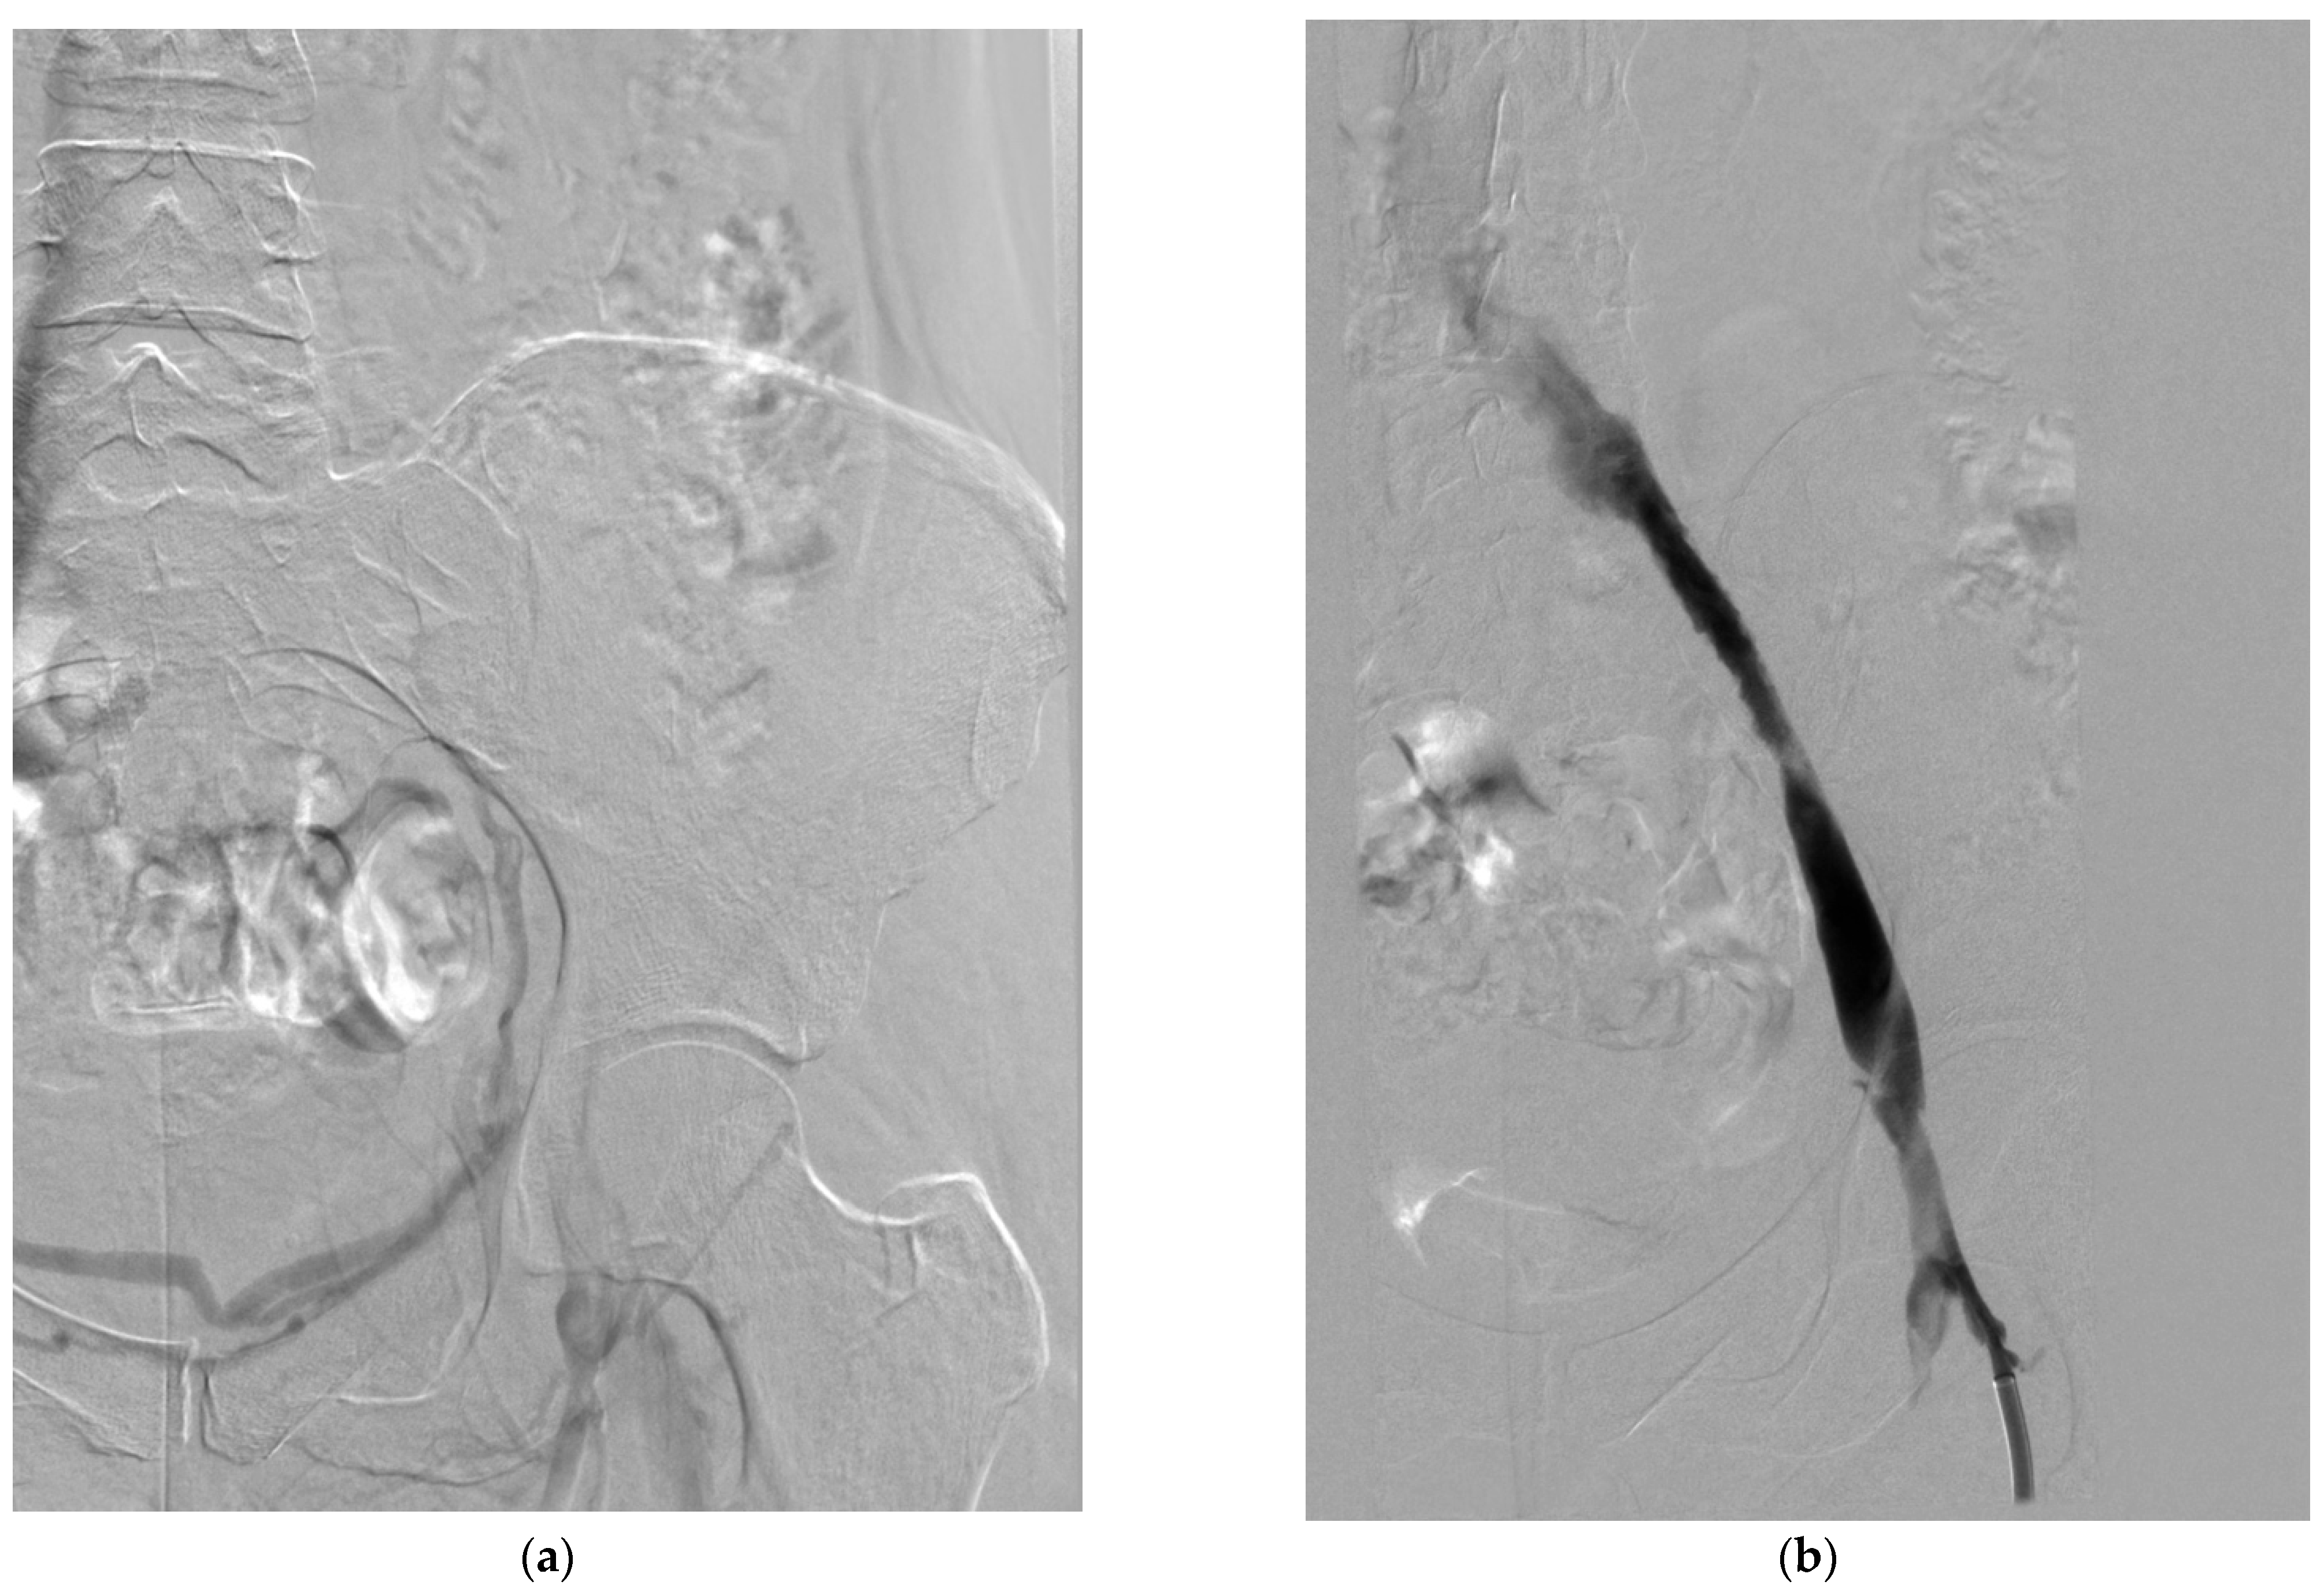

4.3. Pharmacomechanical Thrombectomy

4.3.1. Techniques and Devices

- Power pulse delivery: The AngioJet system can be used in “power pulse mode,” where thrombolytic agent is forcefully injected into the thrombus, allowed to dwell for 20–30 min, and then removed using the standard thrombectomy mode [70]. This technique has been shown to reduce procedure time and thrombolytic dose compared to standard CDT [76].

- Percutaneous mechanical thrombectomy with thrombolysis: This approach involves initial mechanical thrombectomy followed by a short-duration thrombolytic infusion (typically 4–6 h) to address residual thrombus [72]. This sequential approach may be particularly useful for extensive or partially organized thrombi [73].

- Vedantham, S.; Vesely, T.M.; Sicard, G.A.; Brown, D.; Rubin, B.; Sanchez, L.A.; Parti, N.; Picus, D. Pharmacomechanical thrombolysis and early stent placement for iliofemoral deep vein thrombosis. J. Vasc. Interv. Radiol. 2004, 15, 565–574. [Google Scholar] [CrossRef] [PubMed]